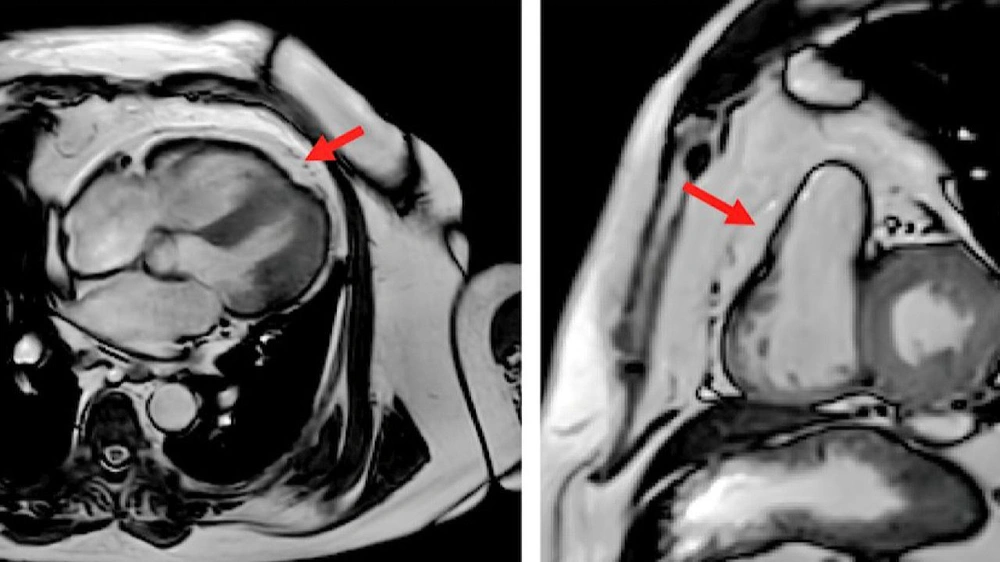

وقال خالد النمر من خلال صحفته الرسمية عبر منصة إكس : " الدهون حول القلب(EAT)تُصَنِّع هرمونات التهابية تُسَرِّع التهاب شرايين القلب التاجية وترتبط بتضيقها وبحدوث الجلطات فيها خاصةً اذا زادت فوق ٥ ملم في السماكة وهي أخطر من دهون البطن ودهون منطقة الحوض " .